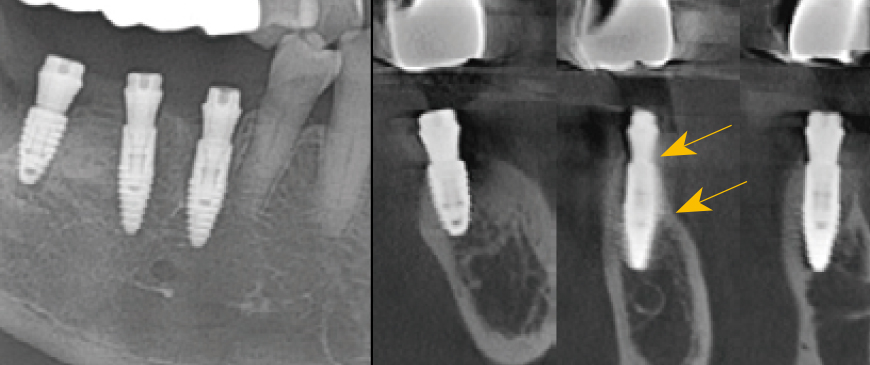

Fig 8

Postoperative panoramic and CBCT radiographs revealed minimal buccal bone thickness around the first molar implant, with the machined cuff of the BD Cuff occupying this space (indicated between the two arrows).